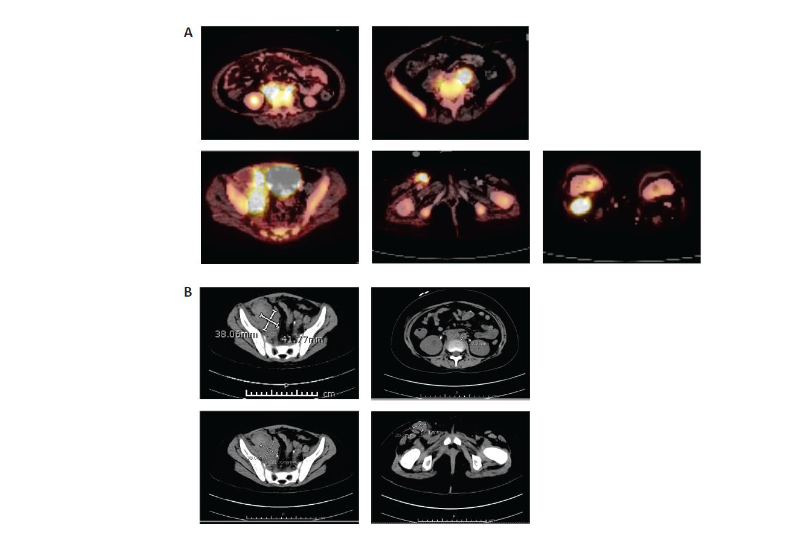

At relapse, she presented with eye pain and swelling, fever, diffuse pain, and blasts in the peripheral blood. Her bone marrow showed over 90% B-cell leukemia blasts that were CD19+ whereas her cerebrospinal fluid was negative. A CT scan to evaluate her eye pain was performed and showed preseptal soft tissue stranding over the left globe, but no signs of orbital cellulitis or overt extramedullary disease. She was treated for preseptal cellulitis, and her symptoms improved.The patient was reinduced with mitoxantrone, vincristine, asparaginase erwinia chrysanthemi, and dexamethasone per COG protocol AALL1331. Following reinduction therapy, her day 35 bone marrow evaluation revealed 47.5% blasts by FCM MRD (CD19+, CD22+ blasts). Given her r/r CD19+ B-ALL, the decision was made to pursue CAR-T cell therapy with tisagenlecleucel. Leukapheresis was performed after recovery from reinduction therapy without any difficulty. She had no peripheral blasts at the time of T-cell collection. There were no complications with the manufacturing of the product.She was then treated with inotuzumab. Disease evaluation after one cycle revealed FCM 6.2% CD19+ leukemia blasts. At this time, she had biopsy-proven new extramedullary disease noted on imaging in her inguinal, retroperitoneal, and cervical lymph nodes as well as in her calvarial bones, left zygomatic arch, and maxillary sinus. Given her suboptimal extramedullary disease control, the patient received aggressive bridging therapy with etoposide and cyclophosphamide followed by salvage escalating-dose blinatumomab.After one cycle of blinatumomab, bone marrow was FCM MRD positive (0.9% CD19+, CD22– blasts) and magnetic resonance imaging evaluation of extramedullary disease sites revealed disease progression (increase in right inguinal nodal mass, stable right iliac and retroperitoneal lymph nodes, progression of soft tissue mass in body orbits that extended into the superior and lateral extraconal orbits, and persistent calvarial marrow involvement with new soft tissue lesions within the left frontal and right temporal calvaria) that was biopsy proven (CD19+ blasts in right inguinal groin lymph node). She developed persistent fevers and clinical concerns for hemophagocytic lymphohistiocytosis and received intravenous (IV) immunoglobulin dexamethasone, and etoposide to control these symptoms during bridging therapy prior to CAR-T cell therapy.Disease staging prior to lymphodepleting chemotherapy demonstrated bone marrow FCM MRD 0.9% CD19+ blasts. A PET scan pre-tisagenlecleucel infusion (Figure 2) revealed periorbital, gingival, extra-axial, calvarial, sinus, inguinal, retroperitoneal, and diffuse bony disease involvement.

Figure 2. Pre–CAR-T cell therapy abdominal (A) PET and (B) CT scans. CAR, chimeric antigen receptor; CT, computed tomography; PET, positron emission tomography.